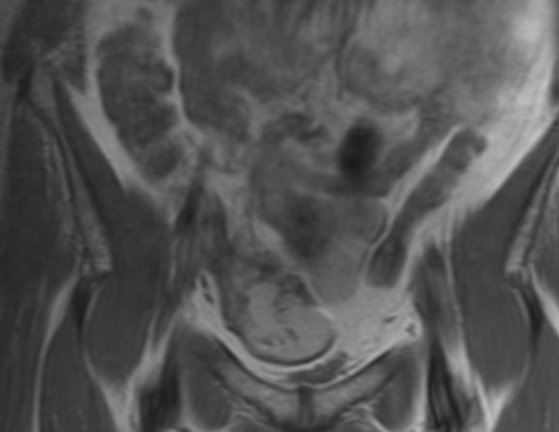

Cecum caecum syndrome